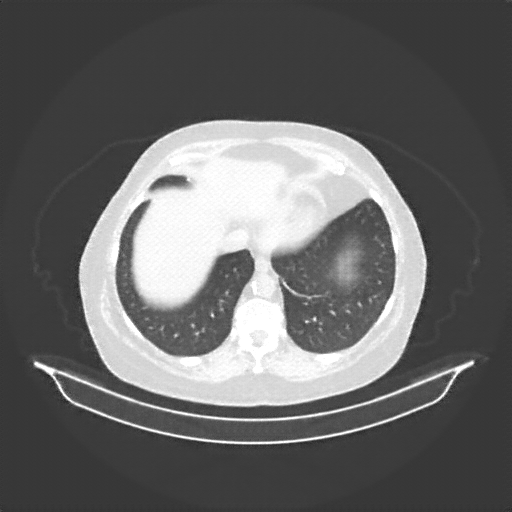

Original VENOUS CT scan

Lung window (WL -600, WW 1500 β†’ Low βˆ’1350, High +150)

Mediastinum window (WL 40, WW 400 β†’ Low βˆ’160, High +240)